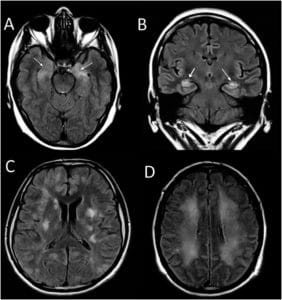

There are many autoantibodies which are useful for the diagnosis of different types of AD, the ideal is to combine them with other diagnostic tests such as electroencephalogram (EEG), nuclear magnetic resonance (MRI) and/or preferential cancer screening, you can obtain an important clinical picture to complement the range of pathologies that manifest with their symptoms.

One of the important things to highlight is that various studies have detailed cases of autoimmune encephalitis that are accompanied by seronegativity in autoantibody tests, to the point that some doctors recommend starting immunotherapy in "cases of symptoms with positive criteria" for AD but in the absence of positive tests for autoantibodies.

When we are faced with an encephalitic disorder of unknown or unclear etiology, we must always rule out alterations in autoimmune mechanisms when symptoms develop rapidly (in a few days or weeks), especially if they are accompanied by signs of inflammation in the brain. CSF or with pathological neuroimaging studies, and whether the clinical and immunological characteristics respond to immunotherapy.

Furthermore, when the serum and/or CSF are negative for clinically relevant autoantibody tests, and the symptoms suggest a possible encephalopathy, we consider the use of research laboratories to rule out any false-negative results. Thanks to this mechanism, the autoantibodies that we know today have been discovered.